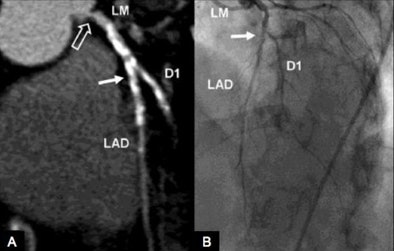

![]() |

| Above, contrast-medium enhanced retrospectively ECG-gated coronary DECT angiography (A) and coronary catheterization (B) in a 75-year-old woman with atypical chest pain and suspected coronary artery disease. Anatomic coronary CTA reconstruction was performed using 70% of the high-energy and 30% of the low-energy x-ray spectrum of the rest scan and shows heavily calcified stenosis (solid arrows) of the proximal LAD and D1 branch in good correlation with invasive coronary catheterization, as well as ostial left main stenosis (open arrow) which could not be appreciated at coronary catheterization. The myocardial blood pool is analyzed by superimposing DECT-based iodine maps onto grayscale multiplanar reformats of the myocardium in short axis views, from which the iodine content in the voxels had been digitally subtracted using the Heart Perfusion Blood Volume application of the DECT reconstruction algorithm. Adenosine stress DECT (C) and stress perfusion cardiac MRI (D) at a mid-ventricular level both show ischemia (arrows) involving the anterior and anteroseptal left ventricle which is partially reversible at rest (E, F). Neither DECT after six minutes (G) nor delayed-enhancement cardiac MRI (H) show contrast media uptake in the ischemic territories compatible with stunned but not infarcted myocardium. |